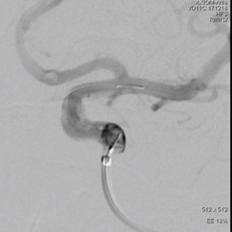

球囊首次扩张,支架展开,首次造影图示动脉瘤近端贴壁不良,有造影剂渗漏至动脉瘤腔内,故再次充盈球囊扩张支架近端。

再行造影见动脉瘤不显影,无造影剂渗漏,血管重建满意。

3D重建图示支架贴壁良好。